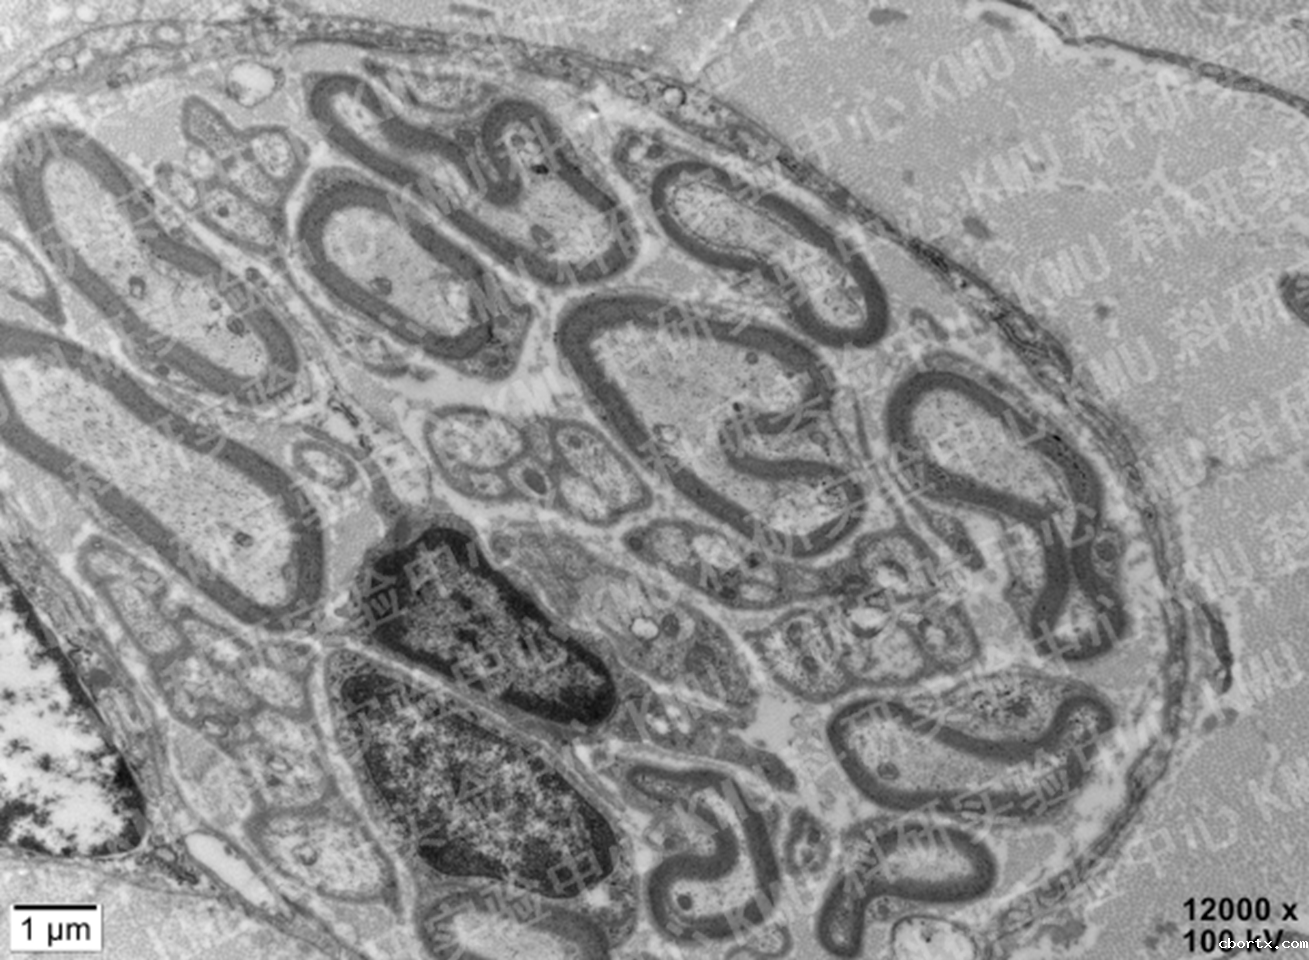

超薄切片技术+透射电子显微镜:

神经髓鞘(18luck备用登录 李丽梅教授课题组)

支气管纤毛(不动纤毛综合征诊断)